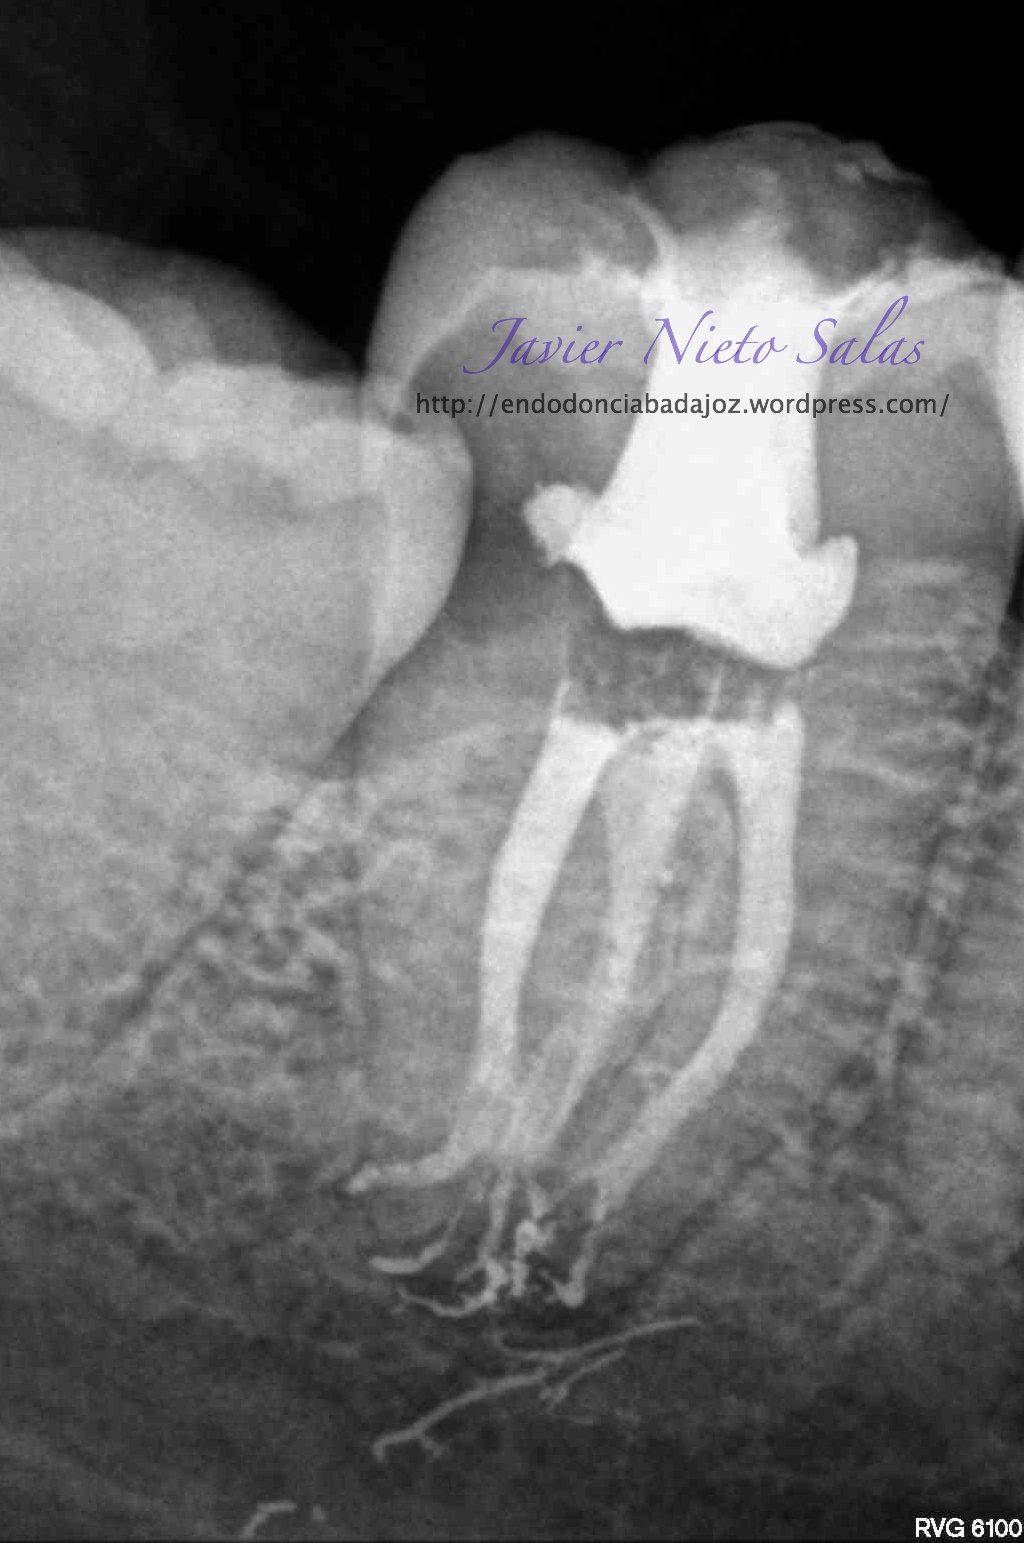

En el siguiente caso:

Se trata de una caso con una clasificación Tipo IIIb por el método de Min, ya pudimos sospechar que se trataba de un conducto en C:

Así podemos modificar nuestra técnica de obturación sabiendo que se trata de un sistema de conductos complicados